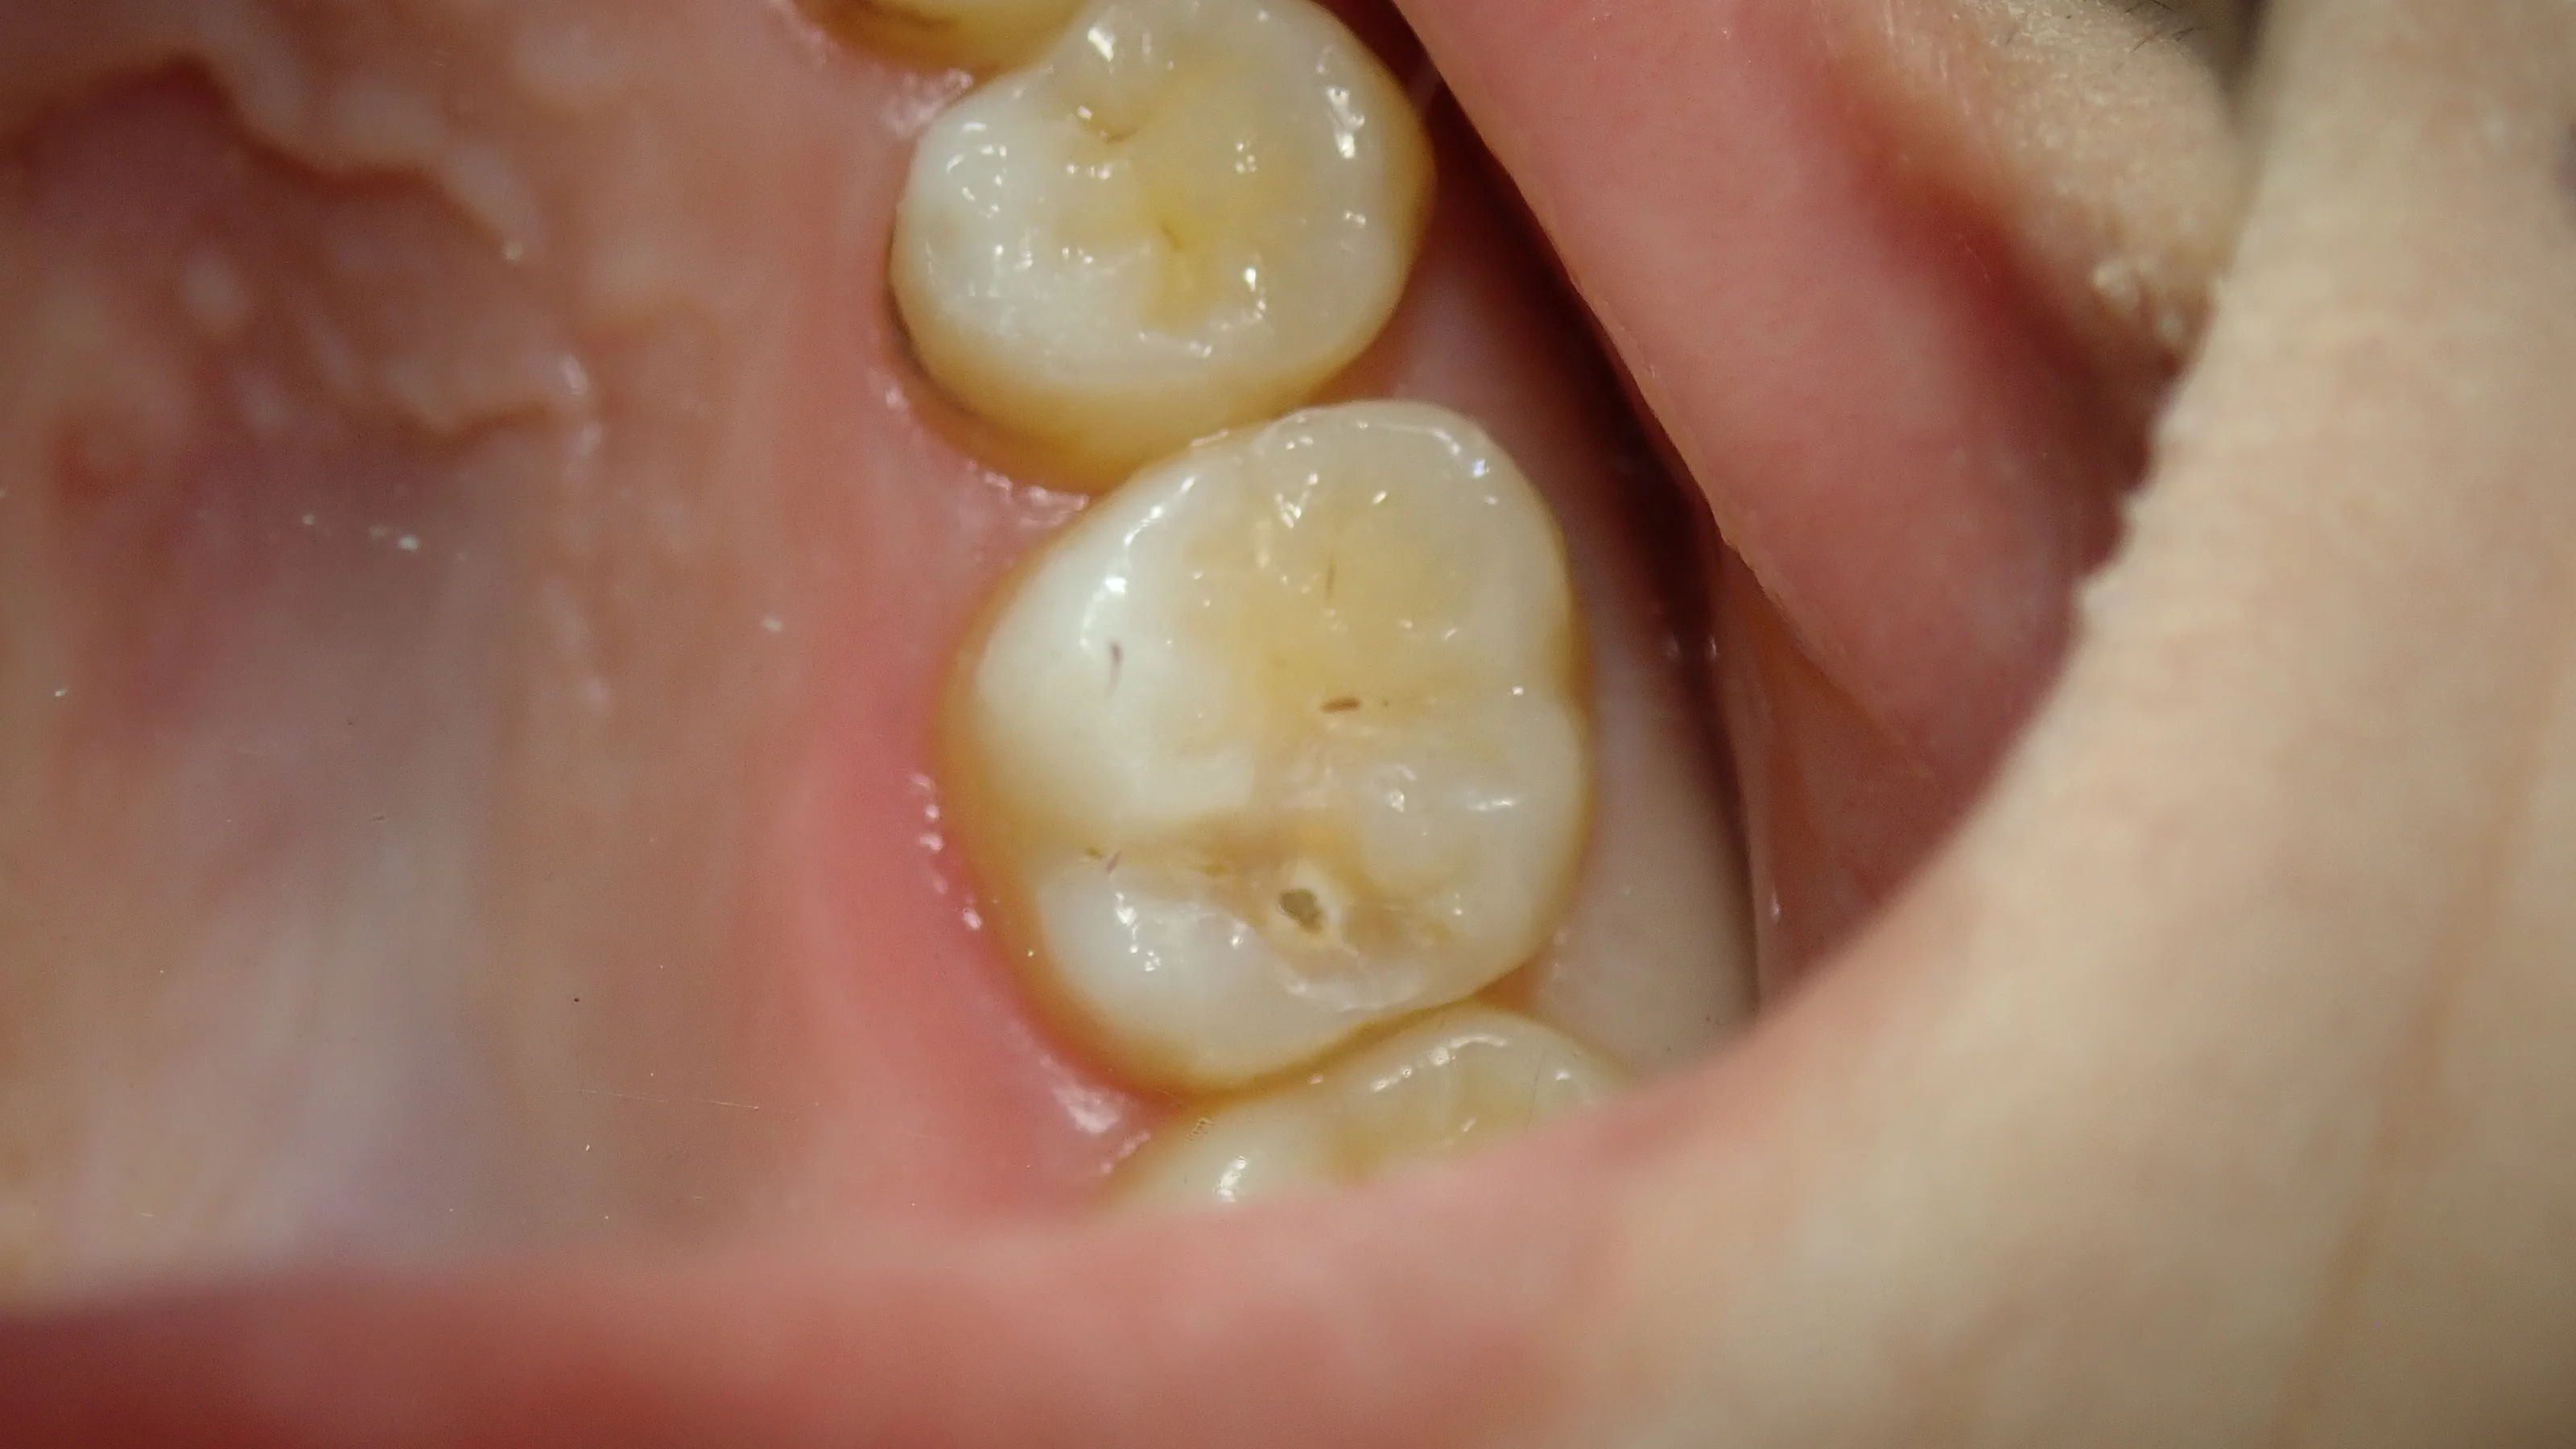

完全に虫歯を取りきると・・・

ものすごく大きい状態でした。

良くも悪くも変に削られておらず、歯を非常に多く残すことが出来たため、そのまま保険内でコンポジットレジンで治療させてもらいました。

術後が、こちらです。